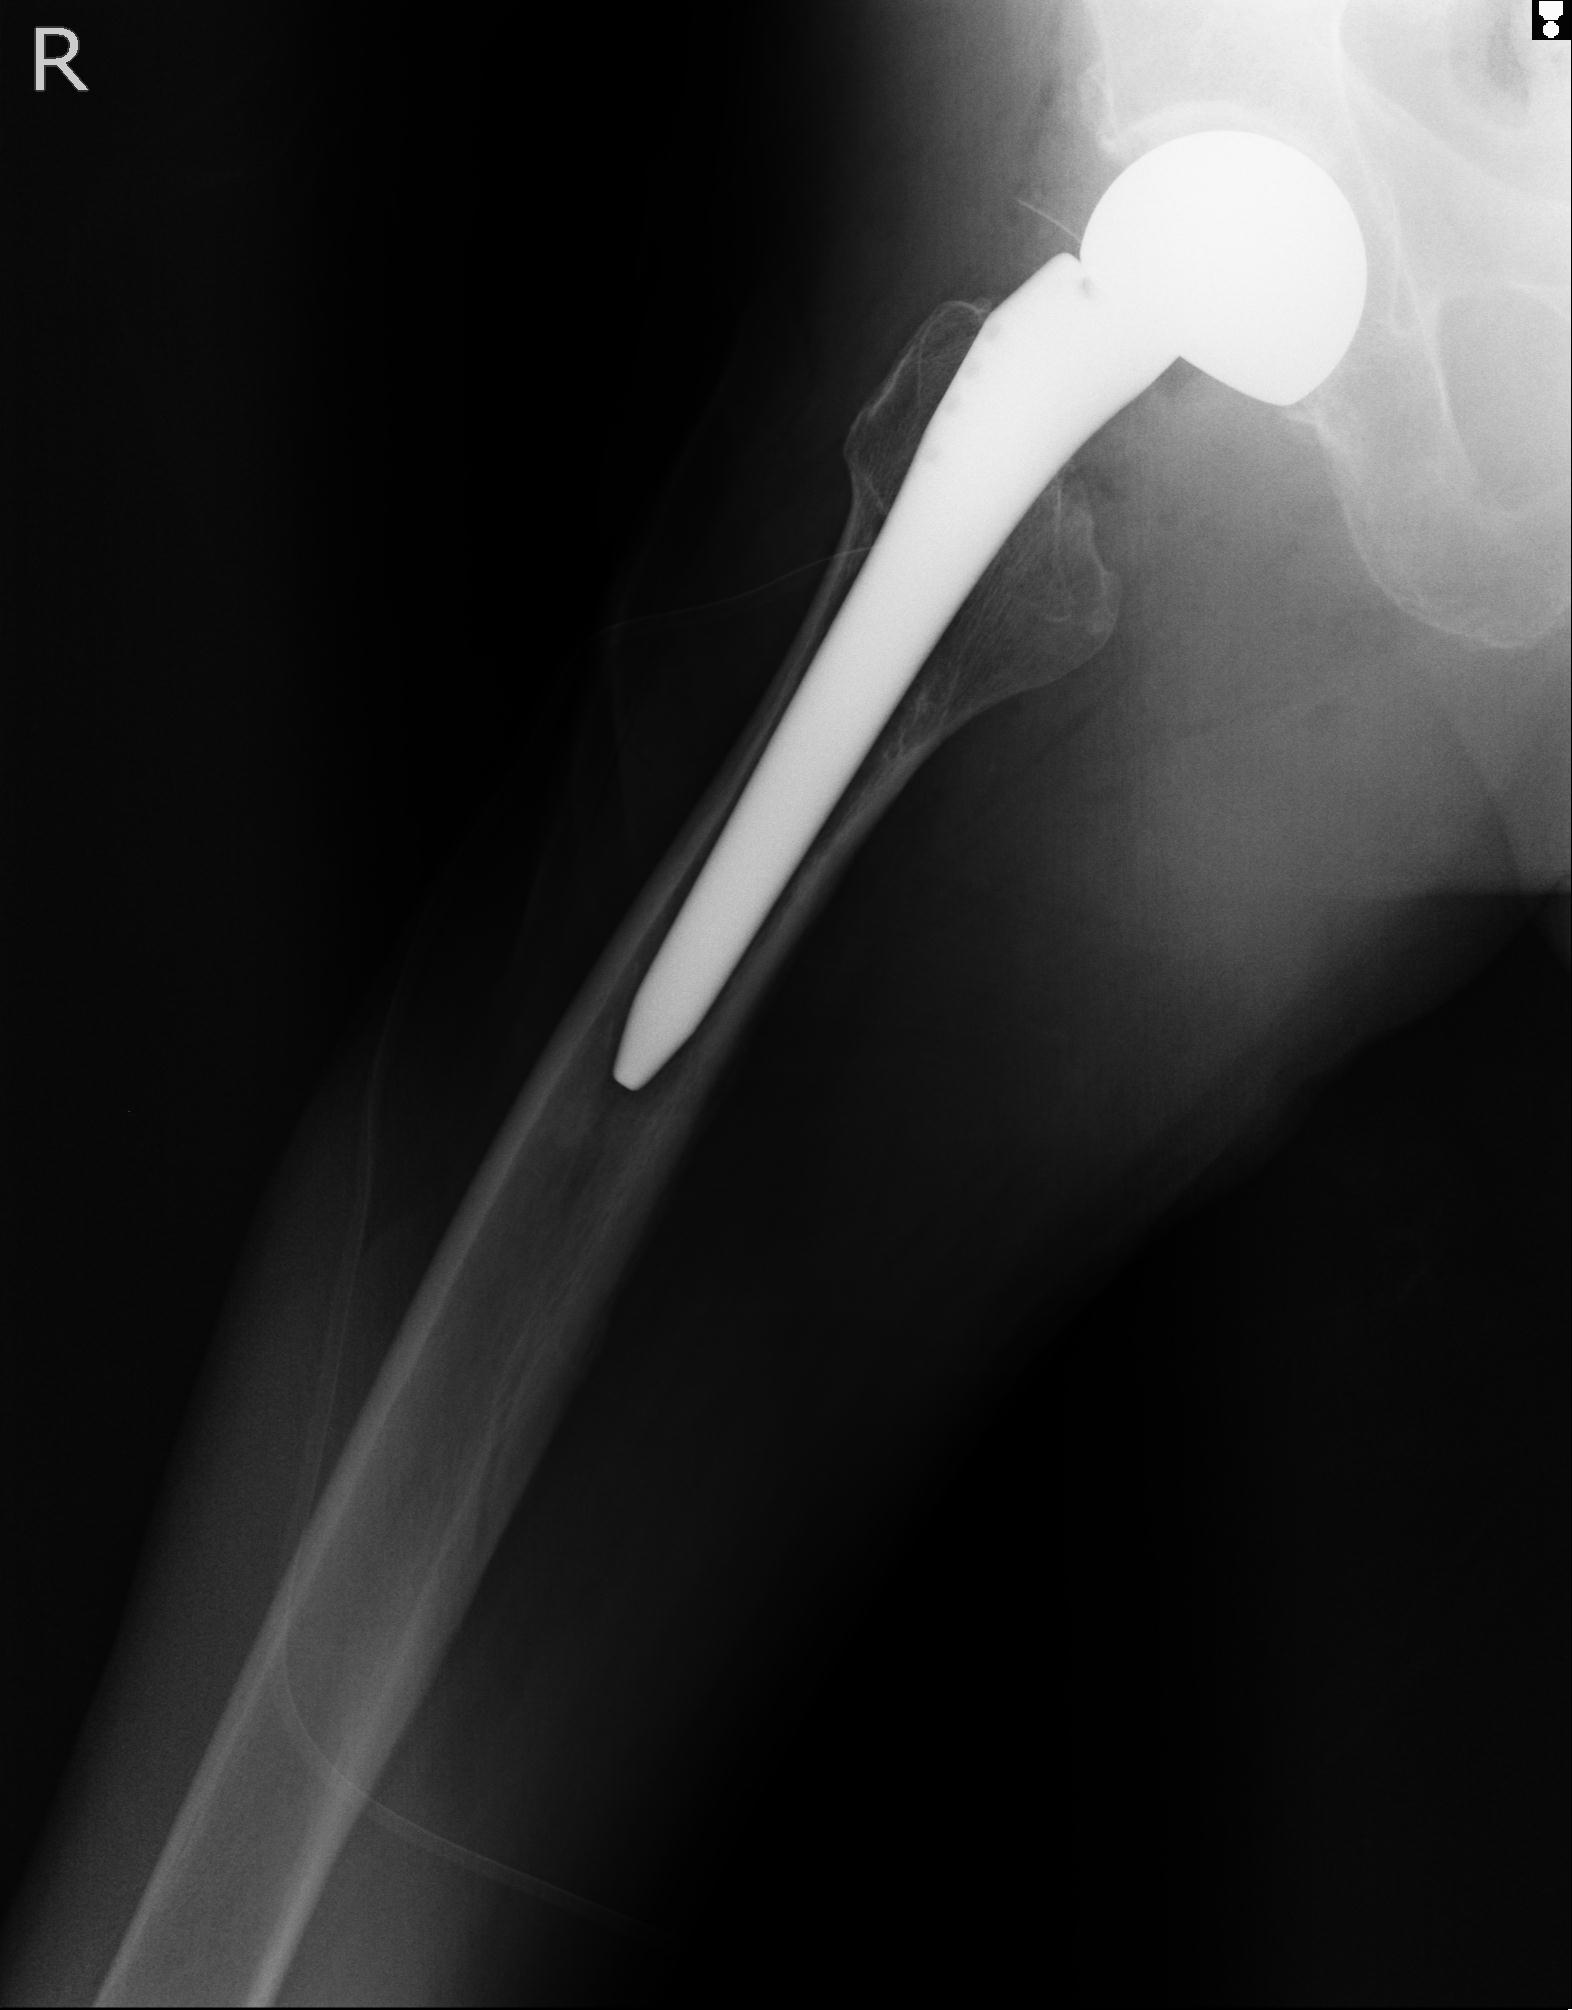

110286 2/17 股関節 2R 74歳女性 右人工骨頭

82084 1/14 1/20 股関節 2R 78歳男性 右人工骨頭